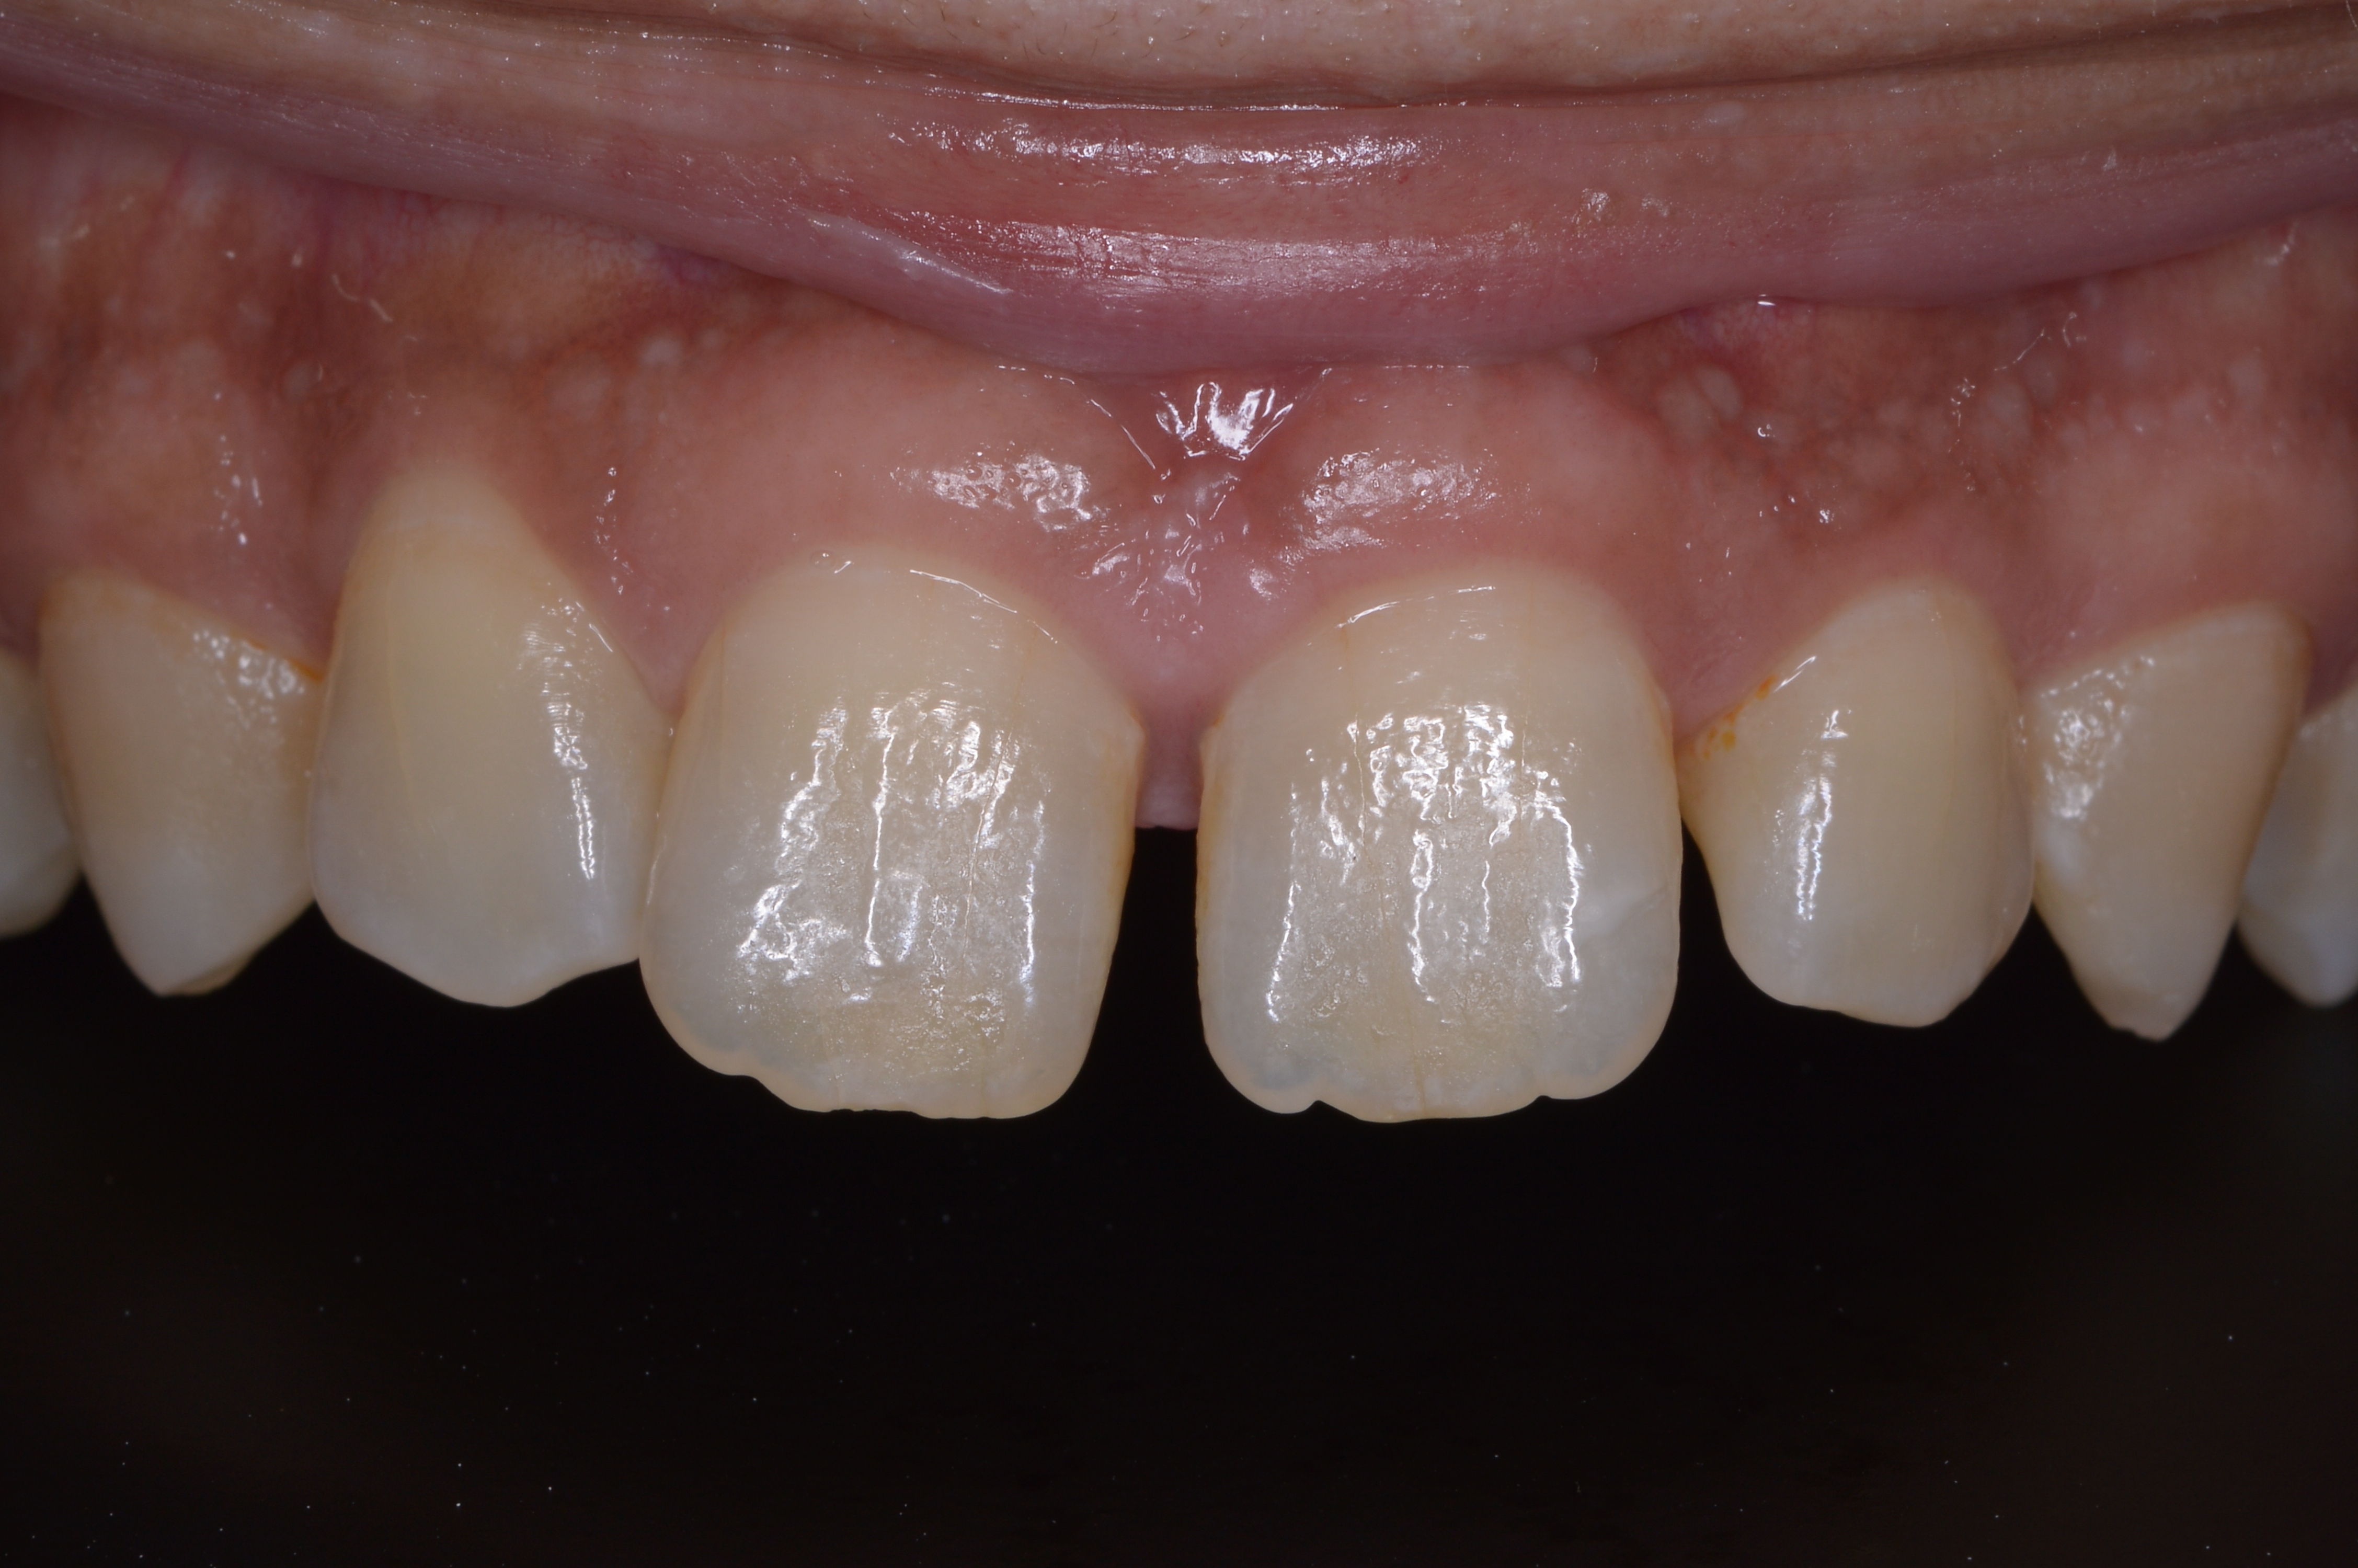

今回は「ダイレクトボンディング」で、すきっ歯を目立たなくした例です。

「ダイレクトボンディング」は歯と同じ色の樹脂コンポジットレジン(CR)を直接歯に盛ることで審美的な治療をする治療方法です。

隙間に盛るだけなので、歯を削ることなく治療できますので、自分の歯へのダメージは最小にできると思います。

治療前の写真です。

上の歯の真ん中とその隣の2箇所に目立つ隙間があり、当医院に相談されました。

治療後の写真です。

結構ナチュラルに治せたかなと思います。